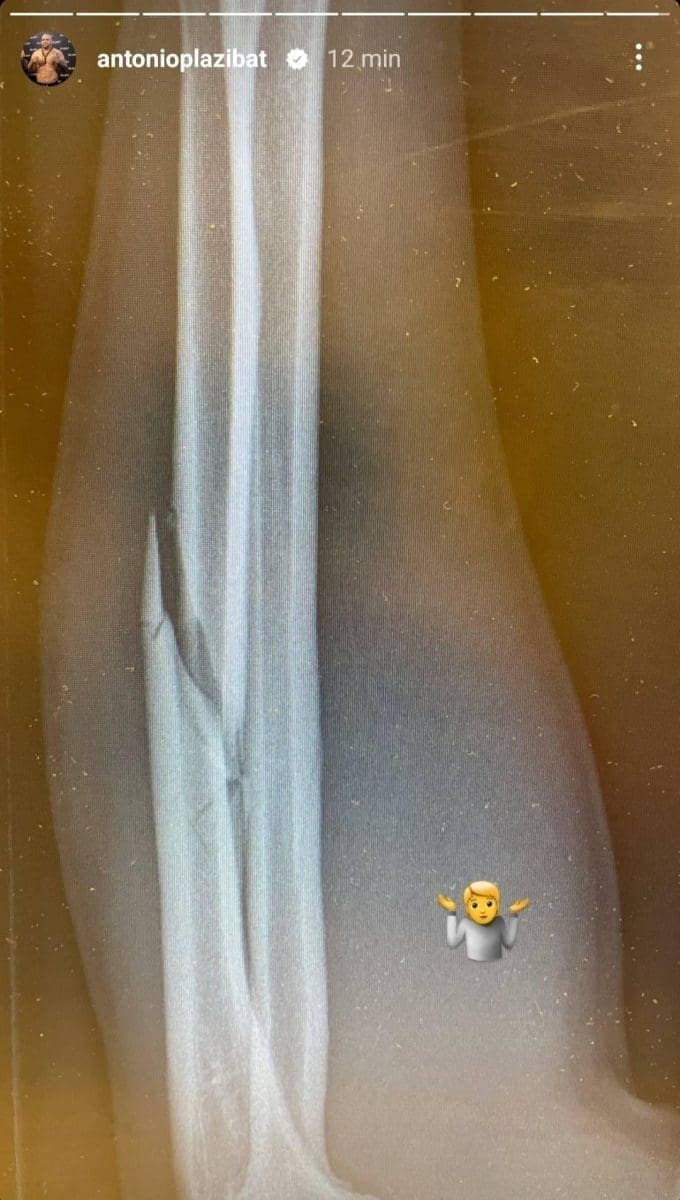

Dakle, Antonio je pretrpio prijelom lakatne kosti (lat. ulna), a kao dokaz prijeloma priložio je rendgensku sliku na kojoj se jasno vidi slomljena kost. Plazibata čeka operacija slomljene ruke, a neko vrijeme će nositi i gips na lijevoj ruci. Već prvu noć imao je velikih problema sa slomljenom rukom, a u ranim jutarnjim satima zatražio je savjet od svojih fanova, piše Fightsite.